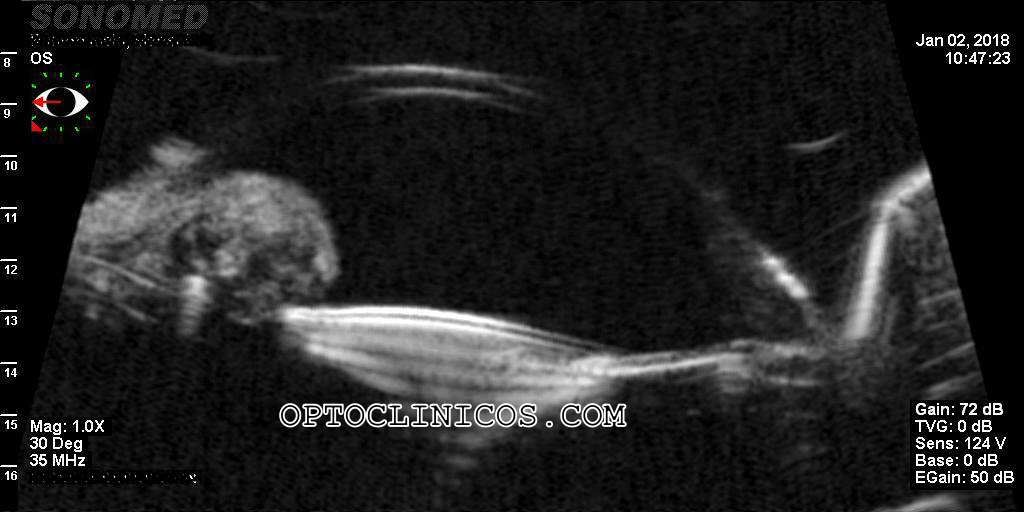

LIO CON TENDENCIA A LUXACIÓN

Nos envían el caso de una paciente en la que se sospecha de masa retroiridiana que presiona su LIO en cámara posterior y con el tiempo y presunto crecimiento, ha hecho que cabalgue sobre el iris, produciéndose luxación parcial a la cámara anterior. Sólo se sospecha, puesto que no ha habido ninguna prueba que certifique qué pasa detrás del iris… hasta que la remiten para hacerle una BMU. La BMU (biomicroscopía ultrasónica) es la única tecnología que puede registrar imágenes detrás de las superficies sólidas del iris, y a tanta profundidad.

Esta es la fotografía bajo el microscopio, donde se puede observar la lente, fuera de saco, pero no los ápticos. ¿Qué estará pasando por detrás en la zona nasal?

BMULIOLUXADA

Esta es la BMU donde podemos ver esa inmensa masa en la zona nasal del iris que está presionando la lente, sacándola de la cámara posterior y obligando a cabalgar sobre el iris.